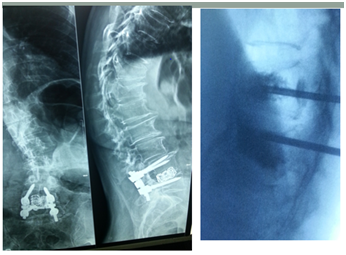

Limited Intervention by Vertebral Augmentation and TLSO & Medical TTT

- 76Years old lady attended with low and mid back pain over the last three months.

- Has a history of L4-L5 cage fusion 15 years before.

- Radiological examination shows:

- Loss of Lumber Lordosis.

- High Degree of Dorso- Lumber kyphosis.

- Wedge compression fractures at D12 &D11.

- Treatment:

- Vertebral Augmentation.

- TLOS Brace.

- Alendronate drugs for her osteoporosis (Figure 8).

Figure 8 Limited intervention by vertebral augmentation and TLSO & Medical ttt.